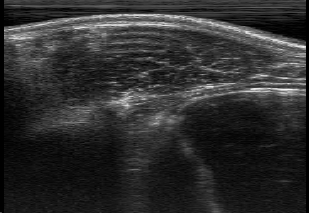

Rib Eye Area (REA). This image dataset consists of ultrasound images of the Longissimus dorsi muscle between the 11th and 13th ribs of cattle. The goal is to automatically calculate the rib eye area (REA), an important region for decision making during cattle breeding. The main challenge is the uncertainty in the REA annotation, since the image is noisy and even experts have difficulty in delimiting the borders of this region. Fig. 3 presents examples of images and the annotation made by a specialist. We can observe that some borders are absent and depend on the subjectivity and knowledge of the annotator. To evaluate the segmentation methods, 76 images with resolution were obtained and labeled by an expert. Due to the number of images, the division of the images in training and testing followed 5-fold cross-validation.

REA dataset. This image dataset has high uncertainty during labeling due to noise from the ultrasound image. In some cases, the border of REA is not completely visible and must be estimated by the specialist. Therefore, the proposed approach becomes essential to obtain accurate segmentation at the edges. The segmentation examples in Fig. 6 show that the baseline was not able to define the REA correctly due to the uncertainty of the labeling. On the other hand, the proposed approach presents results close to the specialist in regions that the border needs to be estimated.